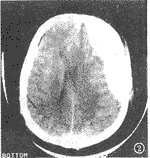

232例颅脑外伤CT随访检查中,61例发现颅内出现异常,其中60例CT复查时间为24h以内,1例为72h。61例中38例为原有的少量出血增多、血肿增大(图1,2)或出现新的血肿(图3,4),15例出现脑挫伤与脑内出血灶,8例出现对冲性脑血肿。

图1 伤后30min头颅CT示两侧额叶及左侧颞、顶叶脑挫伤,蛛网膜下腔出血。

图2 5h后头颅CT复查左额颞顶部硬膜外血肿,蛛网膜下腔出血。